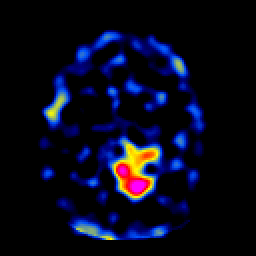

SPECT TL Study #6 -- Slice #34